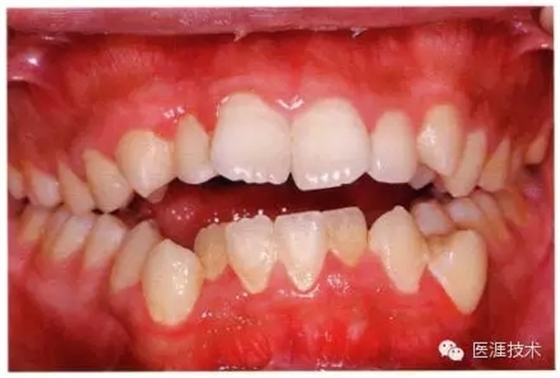

14歲男性牙齦炎的臨床圖像

14歲男性。刷牙狀態(tài)不佳。整顎浮腫性發(fā)紅、腫脹且刺激出血。牙頸部有早期齲(白斑)。